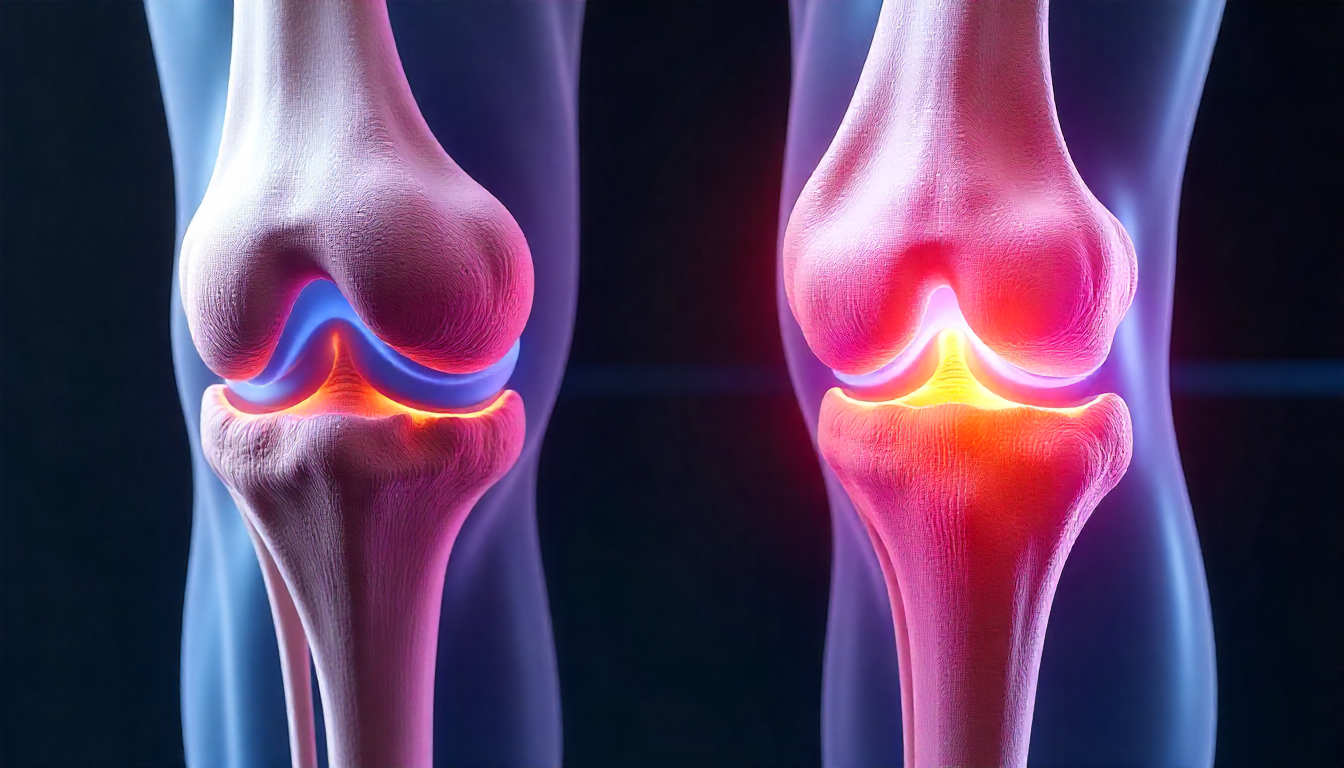

Knee replacement surgery, also known as knee arthroplasty, is a highly effective procedure to relieve severe knee pain and restore function in a damaged knee joint. This surgery is often recommended for individuals suffering from conditions like osteoarthritis, rheumatoid arthritis, or post-traumatic arthritis, where conservative treatments are no longer providing relief. The procedure involves replacing the damaged cartilage and bone of the knee joint with artificial components made of metal and plastic. This comprehensive guide will walk you through everything you need to know about knee replacement, from the signs you might need it to the recovery process.

Deciding on knee replacement is a significant step. It is typically considered when severe knee pain limits daily activities, such as walking, climbing stairs, or even sitting. A patient is usually a candidate if they have tried non-surgical treatments like medication, physical therapy, and injections without success. The decision is made in consultation with a specialized orthopaedic doctor who will evaluate the extent of the knee damage through physical examination and imaging tests like X-rays. A thorough discussion about your health, lifestyle, and expectations is crucial to determine if this surgery is the right choice for you.